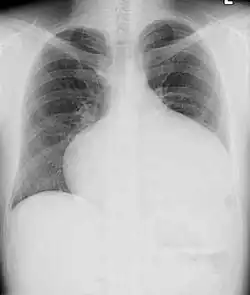

Adults with an uncorrected ASD present with symptoms of dyspnea on exertion (shortness of breath with minimal exercise), congestive heart failure, or cerebrovascular accident (stroke). They may be noted on routine testing to have an abnormal chest X-ray or an abnormal ECG and may have atrial fibrillation. If the ASD causes a left-to-right shunt, the pulmonary vasculature in both lungs may appear dilated on chest X-ray, due to the increase in pulmonary blood flow.[36]